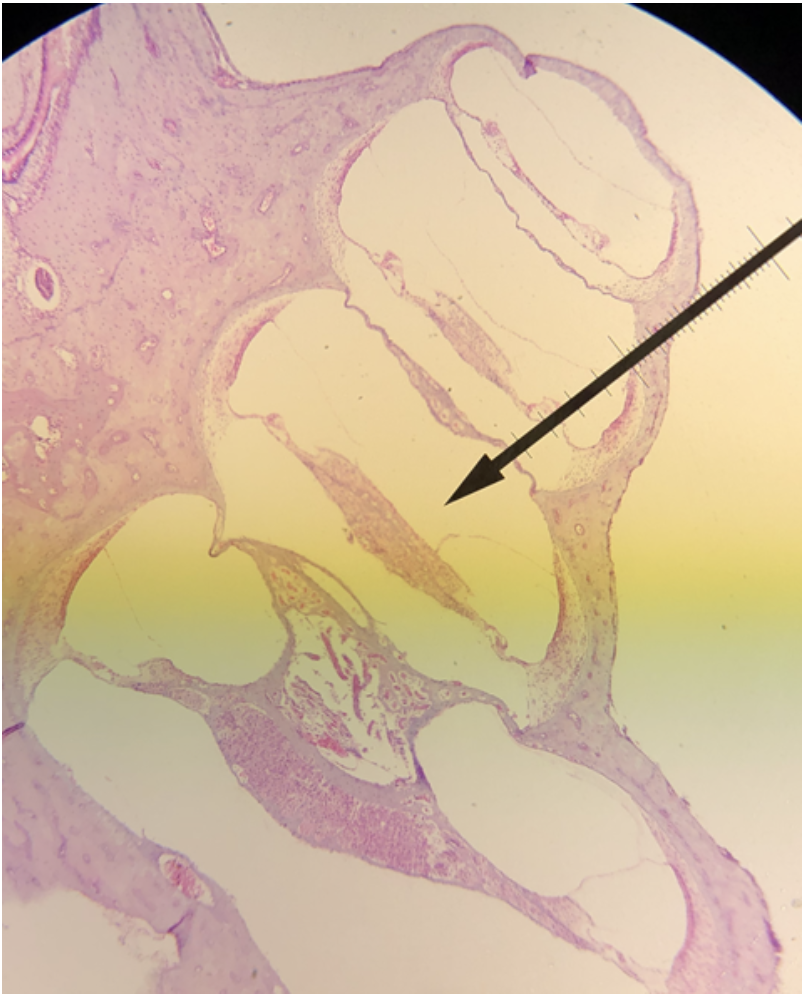

In the image above, identify spaces A-C, and structures D-H.

A. scala vestibuli (vestibular duct)

B. cochlear duct (scala media)

C. scala tympani (tympanic duct)

D. vestibular membrane

E. tectorial membrane

F. basilar membrane

G. spiral organ (organ of Corti)

H. spiral ganglion